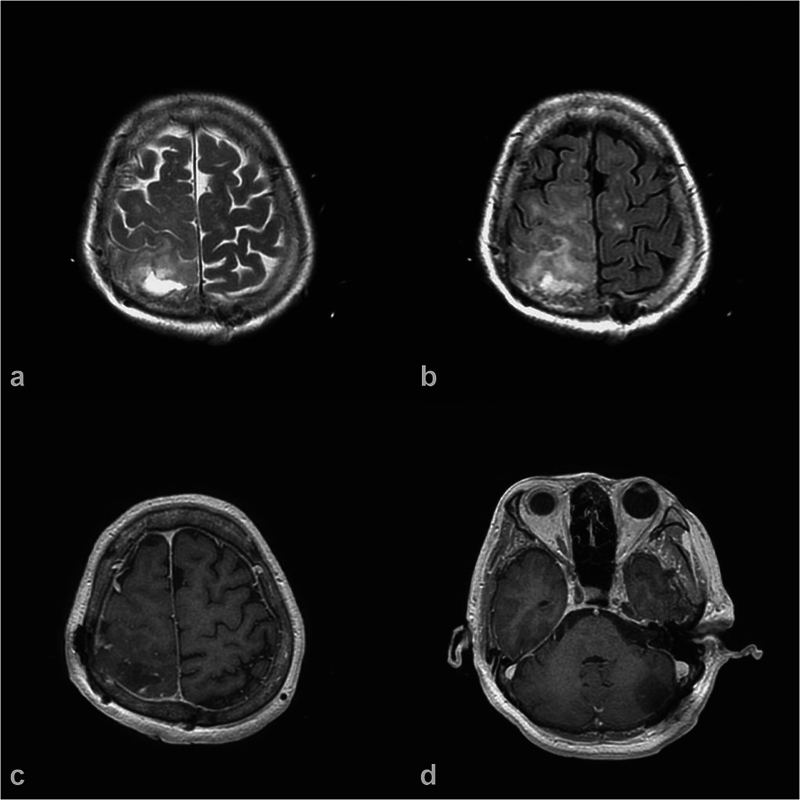

胶质瘤和脑膜瘤是两种常见的原发性脑肿瘤,但在同一患者中同时发生是罕见的。作者想报告一例共存的上顶叶弥漫性胶质瘤,idh野生型,组织学中枢神经系统WHO分级3级和左后窝移行性脑膜瘤,WHO分级1级;在一次手术中成功切除了两个肿瘤。一名68岁女性高血压患者向我们就诊,主诉为左下肢不自主震颤并伴有左上肢刺痛、头晕和颈部酸痛。她被发现在她的右顶叶区有一个病变,在她的左小脑区有一个肿瘤。在与患者详细讨论和全面的术前评估后,作者在一期手术中进行了右侧顶骨开颅和左侧乙状结肠后入路切除这两个肿瘤,证明这两个肿瘤具有两种不同的组织学特征。结论两个相距较远的肿瘤的治疗需要具体情况具体分析。在处理此类病例时,一个重要的方面是决定哪个肿瘤需要先手术,或者两个病变是否可以一次手术同时手术。

Introduction  Gliomas and meningiomas are two common primary brain tumors, but occurring simultaneously in the same patient is a rare entity. The authors would like to report a case of coexistence of a superior parietal lobule diffuse glioma, IDH-wild type, histologically CNS WHO grade 3 and a left posterior fossa transitional meningioma, WHO grade 1; both the tumors were successfully removed in one-stage operation. Case Presentation  A 68-year-old female having hypertension, who presented to us with the chief complaints of involuntary shaking of her left lower limb associated with her left upper limb tingle, dizziness, and neck soreness. She was found to have a lesion in her right parietal region and a tumor in her left cerebellar region. After detailed discussion with the patient and thorough preoperative evaluation, the authors performed a right parietal craniotomy and a left retrosigmoid approach in one-stage operation to remove both the tumors, which were proven to be of two distinct histological identities. Conclusion  The management for two tumors located far apart needs a case-by-case evaluation. An important aspect while dealing with such cases is to decide which tumor needs to be operated first or whether both lesions can be operated at the same time with one-stage operation.